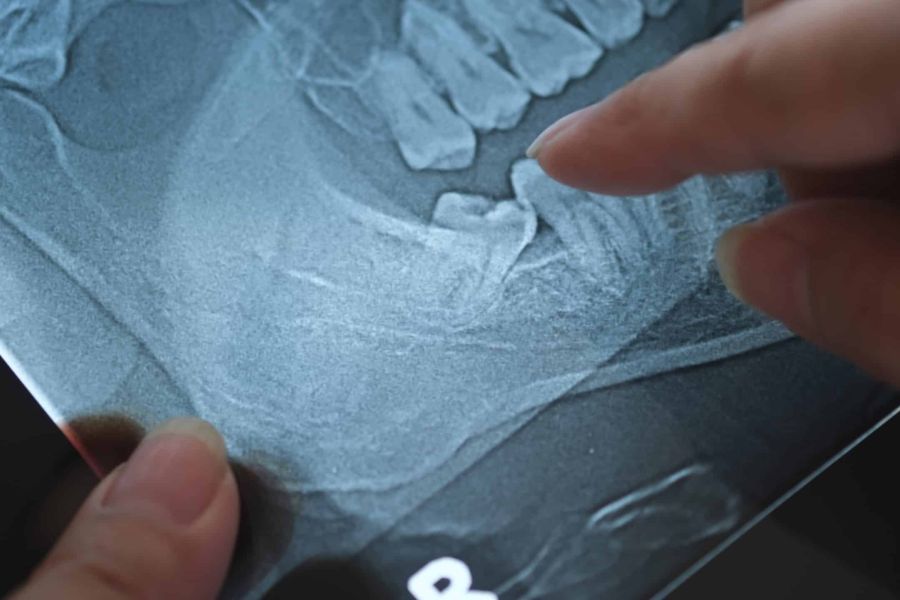

Röntgenbild eines Unterkiefers mit einem schief stehenden Weisheitszahn

Weisheitszähne können im Kiefer oft Probleme verursachen. Ihr verspäteter Durchbruch führt häufig zu Platzmangel, schiefem Wachstum oder Entzündungen. In solchen Fällen ist es sinnvoll, die Weisheitszähne zu entfernen, um Beschwerden oder negative Folgen für die benachbarten Zähne zu vermeiden.

Die Entfernung von Weisheitszähnen erfolgt in unserer Praxis mit modernen Verfahren und unter örtlicher Betäubung. Je nach Lage der Weisheitszähne kann der Eingriff minimalinvasiv durchgeführt werden, sodass das Ziehen so schonend wie möglich verläuft. Dabei achten wir darauf, die Zahnwurzel präzise zu lösen, um umliegendes Gewebe zu schützen.

• Bei schief wachsenden oder verlagerten Weisheitszähnen